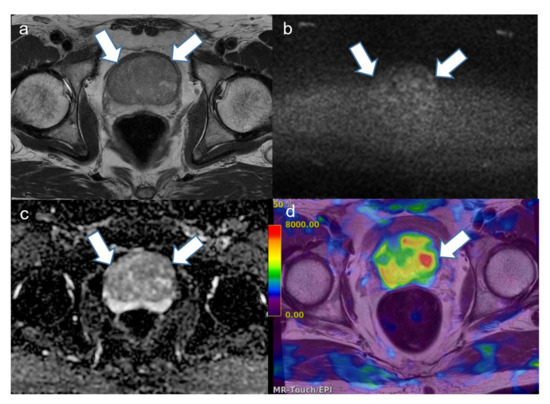

2.4. Image Analysis

4. Discussion